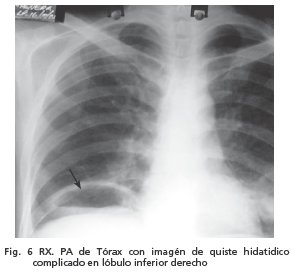

A su ingreso contaba con Rx PA de tórax (fig. 5) pre quirúrgica con imagen radiopaca, homogénea con bordes redondeados, en cuadrante inferior izquierdo de aproximadamente 12 cm de diámetro y en campo pulmonar derecho, en región supradiafragmática, se observa imagen con nivel hidroaéreo de quiste hidatídico roto.(signo de camalote) (Fig. 6)

A los 9 días de la cirugía paciente fue programado para quistectomía de quiste hidatídico roto sin embargo paciente solicita alta. (fig. 6).